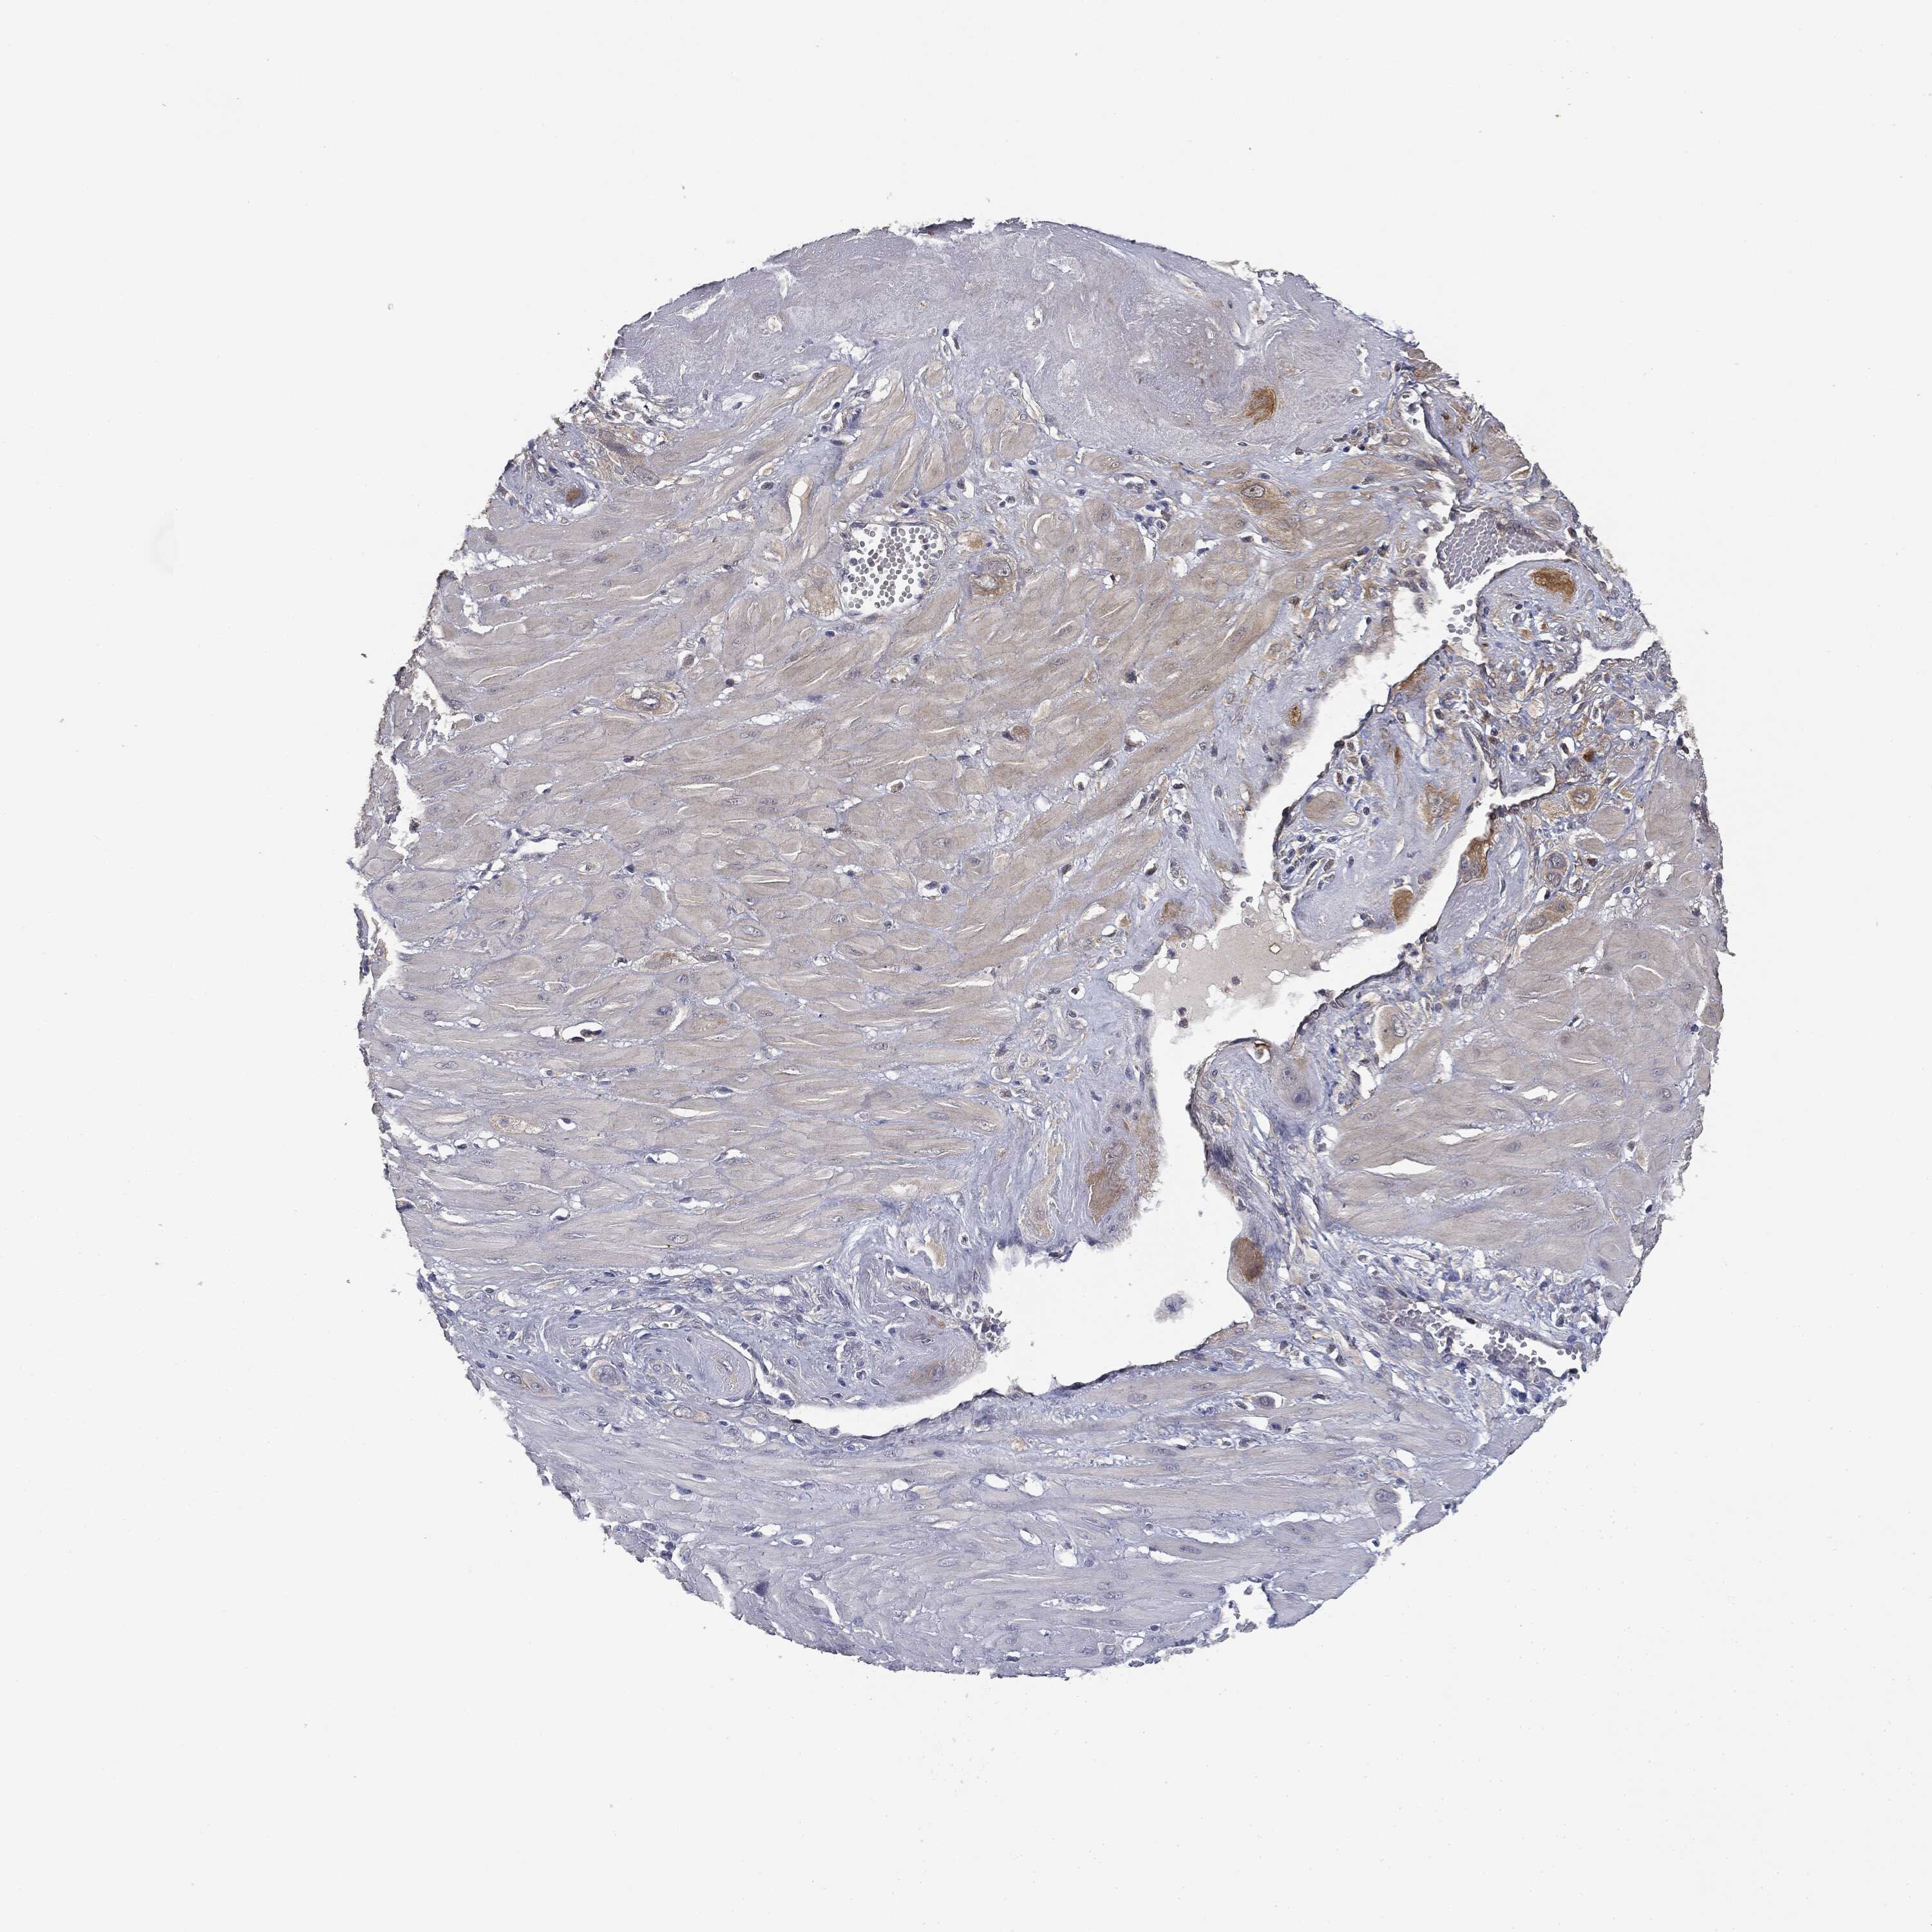

CERVICAL CANCER - Protein expressioni

A mouse-over function shows sample information and annotation data. Click on an image to view it in a full screen mode. Samples can be filtered based on level of antibody staining by selecting one or several of the following categories: high, medium, low and not detected. The assay and annotation is described here.

Note that samples used for immunohistochemistry by the Human Protein Atlas do not correspond to samples in the TCGA dataset.

Antibody stainingi

Antibody staining in the annotated cell types in the current human tissue is reported as not detected, low, medium, or high, based on conventional immunohistochemistry profiling in selected tissues. This score is based on the combination of the staining intensity and fraction of stained cells.

Each image is clickable and will lead to virtual microscopy that enables deeper exploration of all samples and also displays staining intensity scores, fraction scores and subcellular localization as well as patient and tissue information for each sample.

Antibody HPA066153

Squamous cell carcinoma, NOS